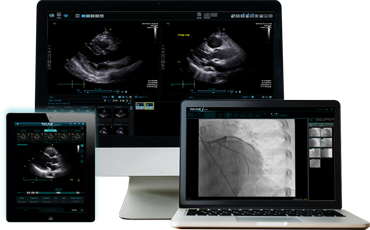

– 빠른 로딩 성능 : 대기 시간을 최소화하여 신속하고 정확한 이미지 뷰어 시스템을 제공합니다.

다양한 이미징 시스템 지원이 가능합니다.

– Compare mode를 통한 한 환자의 영상 비교가 가능합니다.

– Two List mode를 통한 다른 환자와의 영상 비교 및 별개의 시스템으로 활용 가능합니다.

– 다중 뷰어를 통해 효율적인 영상 판독이 가능합니다.

– 사용자의 작업 환경에 맞는 레이아웃을 제공하여 영상 조회가 가능합니다

– 병원의 어디서나 네트워크가 연결되어있다면 컴퓨터로 영상 조회가 가능합니다.

– 간단한 조작법으로 환자 검색 및 영상 조회가 가능합니다.

– 직관적이고 유연한 인터페이스 구성으로 영상을 판독하는 소요 시간을 크게 줄여줍니다.

– EMR / HIS에서의 데이터 활용을 통한 영상 판독이 가능합니다.